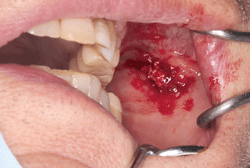

口腔外科 炎症の治療例 府中市の歯科医院 武田歯科医院